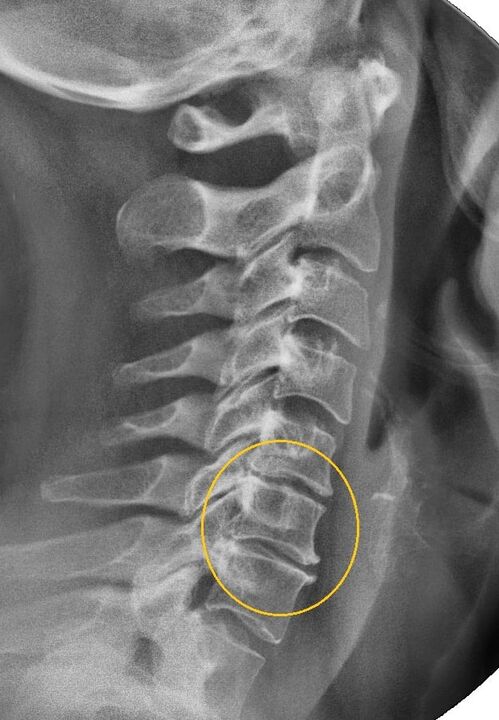

The most informative diagnostic procedure is radiography.Grade 1 pathologies correspond to the first or second radiological stage.The resulting images visualize the typical signs of the disease.

| X-ray stages of cervical osteochondrosis of the 1st degree | Characteristic signs |

|---|---|

| Phase 1 | Small changes in the curvature of the spine in the cervical region, affecting one or more segments |

| Phase 2 | Slight thickening of intervertebral discs, deformation of uncinate processes, direction of lordosis, small growths of bone structures. |